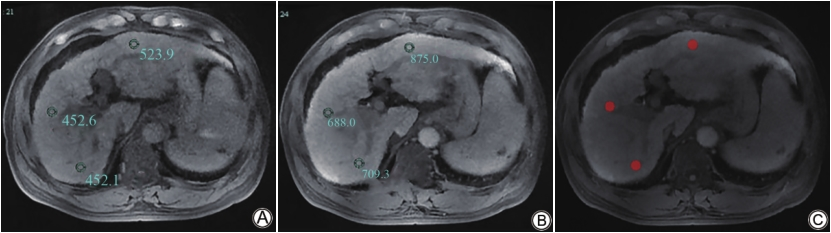

所有病例肝胆期的图像以DICOM格式从PACS (picture archiving and communication systems,PACS)导出、存储,并导入ITK-SNAP软件(http://www.itksnap.org,版本3.7.2)。两名医生分别在PACS和在ITK-SNAP软件上同时行肝胆期感兴趣区(region of interest,ROI)设置,在肝门层面分别选择左肝、右肝前叶、右肝后叶肝实质内设置面积约100±5 mm2的ROI,注意避开血管、胆管、病灶等,保持不同时相的ROI大小、位置尽量一致,以ITK-SNAP软件上肝胆期ROI为参考设置预描期ROI,在相同层面上下各加一层进行三维的勾画(如图1所示)。以左肝、右肝前叶及右肝后叶信号强度(signal intensity,SI)的均值作为全肝平均信号强度SI。肝脏增强前信号强度以SIpre表示、肝脏肝胆期信号强度以SIpost表示,根据公式REHBP=(SIpost–SIpre)/ SIpre,计算出每位患者的REHBP值。